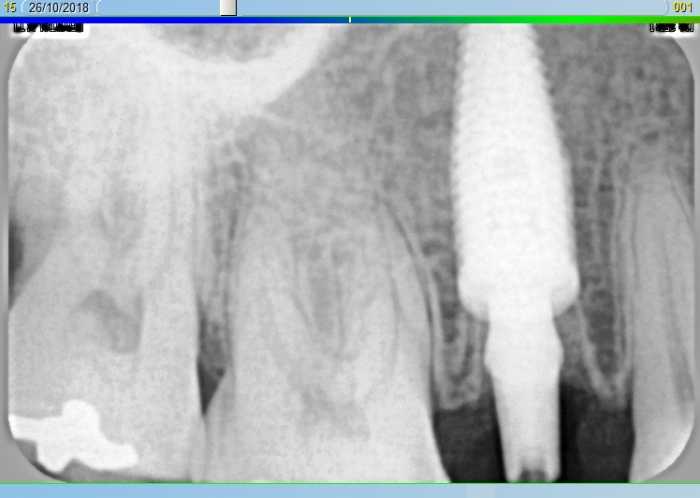

Elemento 15 fraturado

Rx Imediato